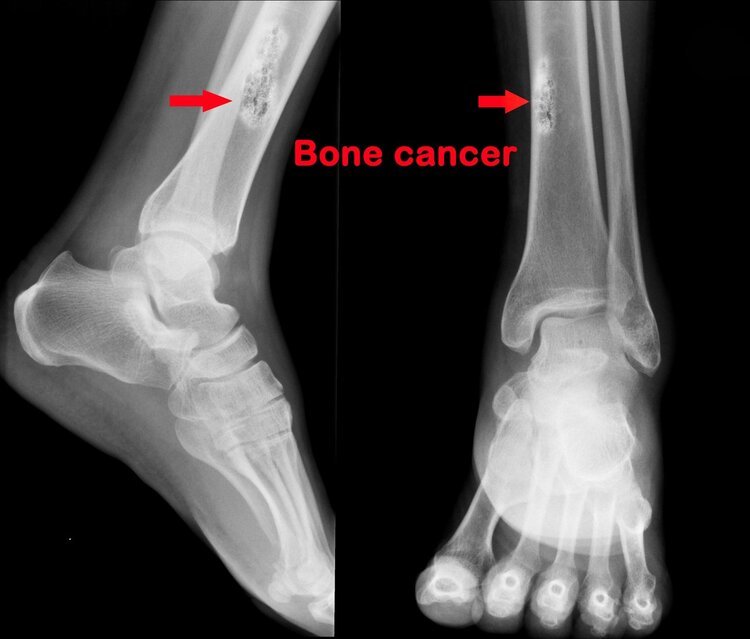

骨肉瘤最常见的临床症状除了肢体疼痛还有关节肿胀。如果青少年出现不明原因的肢体关节肿胀及肿块,晚期局部还会发热发红,常规消肿治疗无效,则要接受医生的建议,及时进行X线片、核磁等检查。

出现以上症状的患者需要尽早前往医院做详细检查。确诊恶性骨肿瘤的检查包括局部的X线、CT扫描、磁共振扫描,必要时要进行增强扫描,由于恶性骨肿瘤易转移到肺,进行胸部薄层CT扫描可以有效发现早期的肺部转移灶。